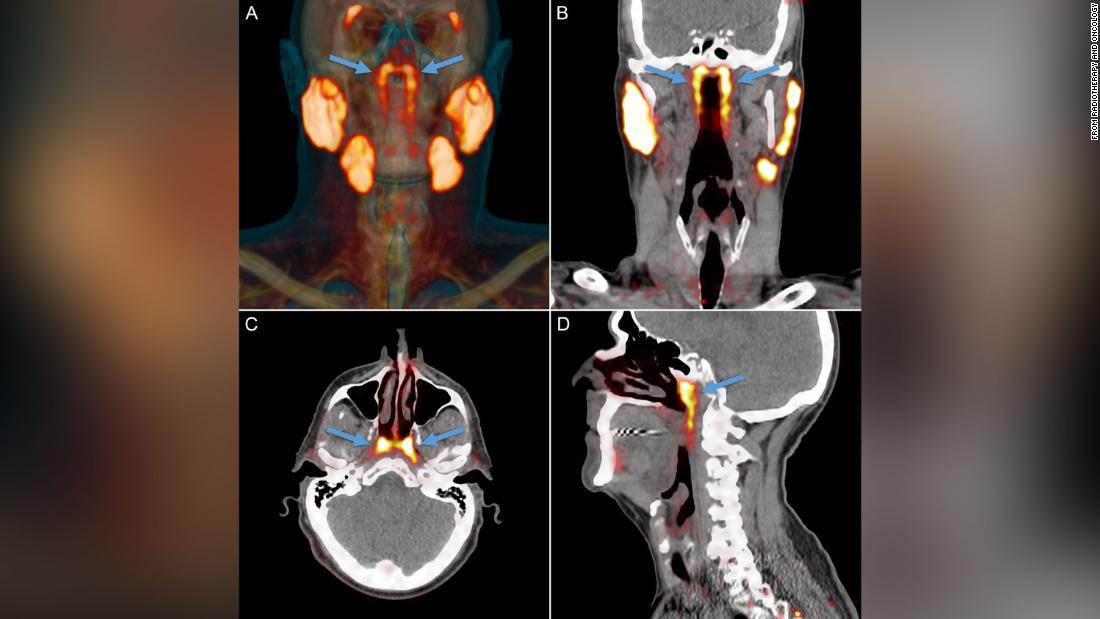

2020.10.22 Thu posted at 11:09 JSTオランダの研究チームが人ののどの奥に未知の臓器を発見した/From Radiotherapy and Oncology

同チームは「tubarial glands」という名称を提案している。この臓器はがんの転移診断のためのスキャン検査で見つかった。

研究チームはさらに、前立腺がんで治療中の患者100人の頭部と頸部(けいぶ)のスキャン画像を調べ、男性1人と女性1人の遺体解剖を行った結果、全員がこの臓器を対でもっていることが分かった。超音波やCTスキャン、磁気共鳴断層撮影(MRI)といった一般的な検査ではこの臓器は見つけられず、前立腺がんの転移を調べるPSMA PET/CTという先端のスキャン検査で初めて見つかった。

PSMA PET/CTスキャンの画像/From Radiotherapy and Oncology論文を発表した研究者は「2020年にこんなものが見つけられるとは思わなかった」と振り返る。